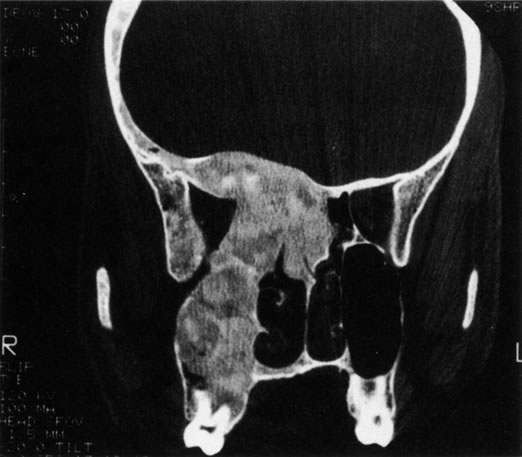

Fibrous dysplasia is a benign disorder characterized by an arrest of bone maturation that results in immature bone and osteoid in a cellular fibrous matrix. This congenital disease usually becomes clinically apparent in children and young adults. Fibrous dysplasia can extensively involve the facial bones and skull.24 The maxillary, frontal, and sphenoid bones are most commonly involved. Maxillary bone involvement can cause nasolacrimal duct obstruction. Involvement of the frontal and sphenoid bones may result in orbital asymmetry from contour deformities, vertical dystopia, and exophthalmos (Fig. 17). Radiographically, fibrous dysplasia appears as an expansile bone lesion with a characteristic ground-glass appearance (Fig. 18). Additional ocular complications include compressive optic neuropathy, oculomotor nerve palsy, and trigeminal neuralgia.25 Involvement of the sphenoid bone may result in narrowing of the optic canal, with secondary compressive optic neuropathy. Definitive treatment entails unroofing the optic canal by way of a transcranial approach, although high-dose steroids can be used as a temporizing measure.

Fig. 18. Fibrous dysplasia that involves the frontal, sphenoid, ethmoid, and zygomatic bones illustrates the characteristic ground-glass appearance of this disorder.